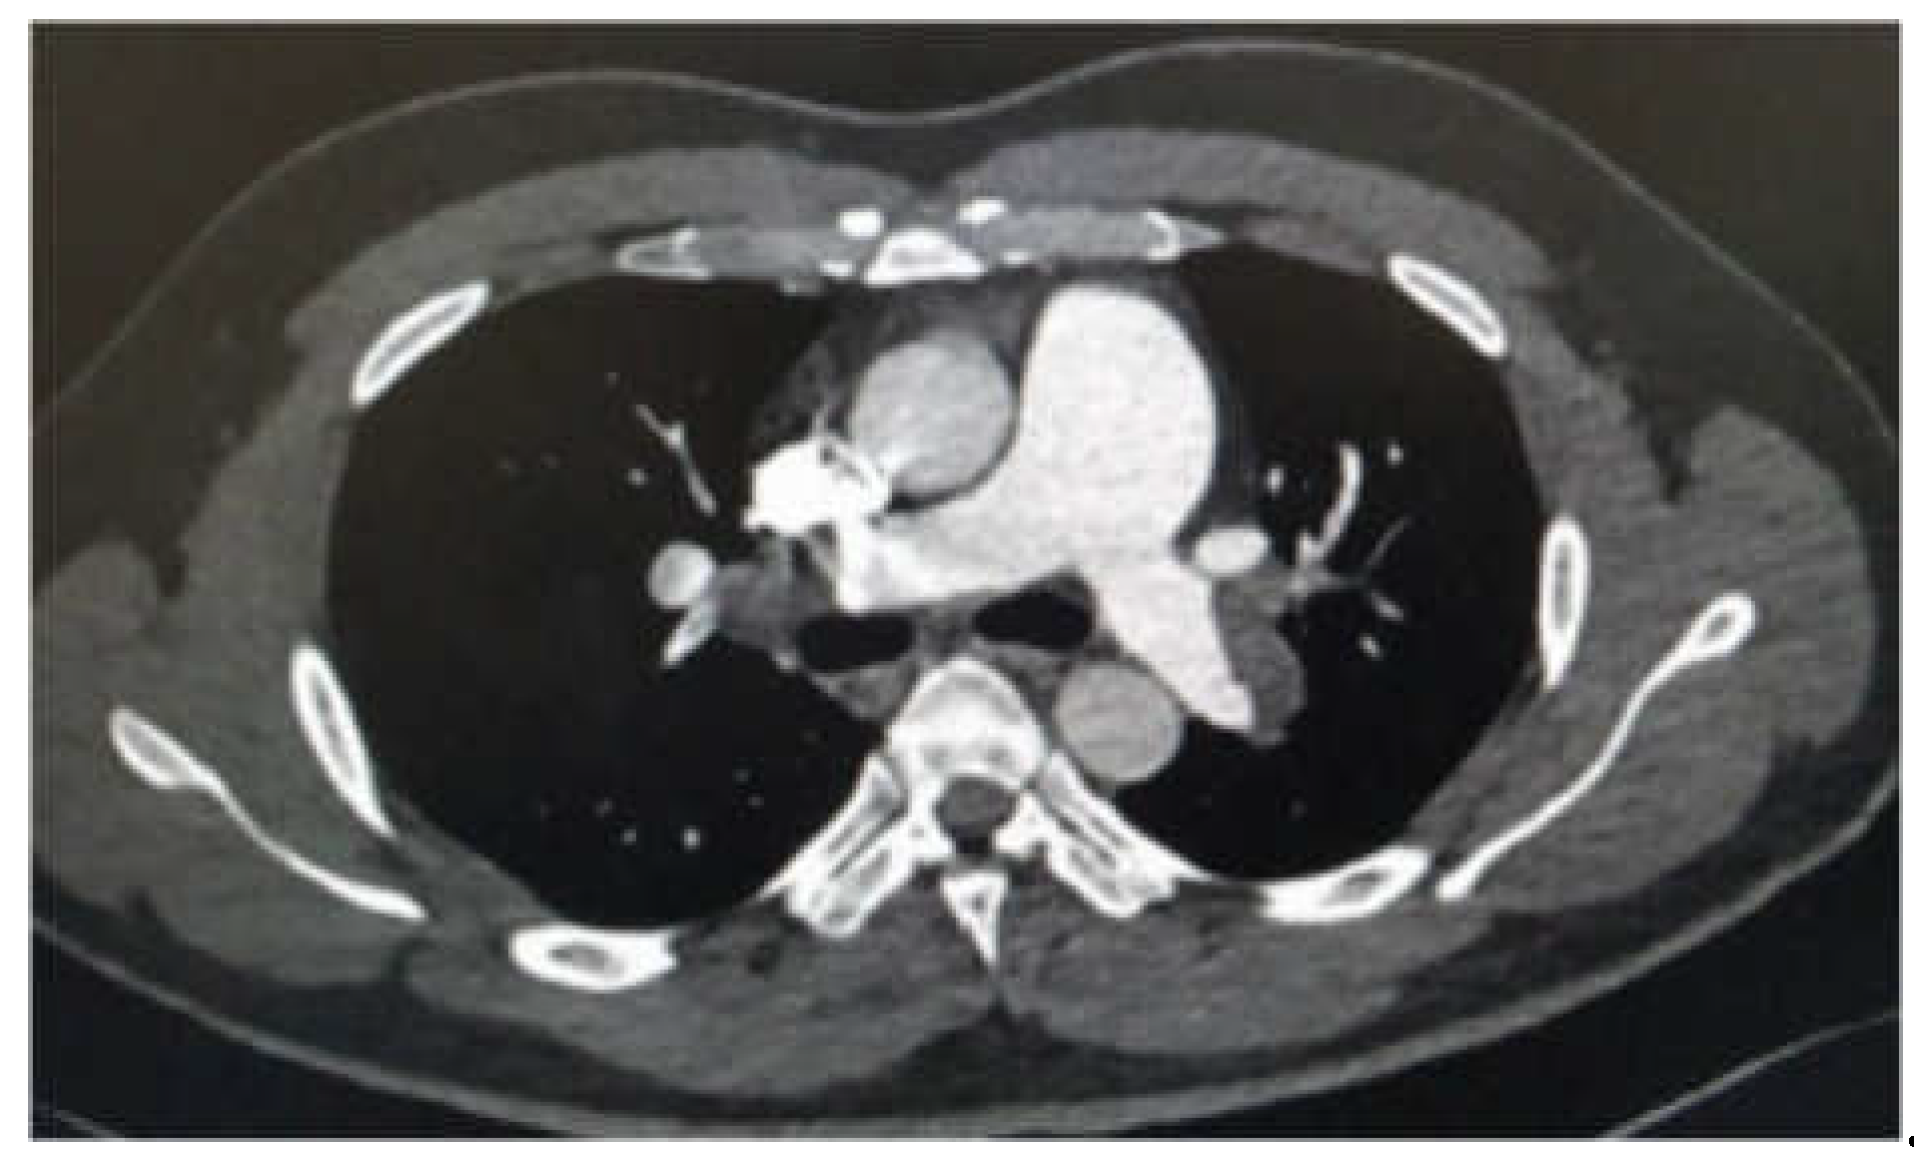

Chest X-ray was normal, and the Electrocardiogram showed sinus tachycardia at 110 bpm with inverted negative T waves in the anteroseptal and inferior precordial leads. Labs results showed D-dimer level at 1700 ng/ml and negative troponin. A thoracic CT angiography was performed showing massive bilateral proximal pulmonary embolism with indirect signs of severity (dilatation of the right ventricle). (Figure 4).

Figure 4. CT scan showing massive bilateral proximal PE.